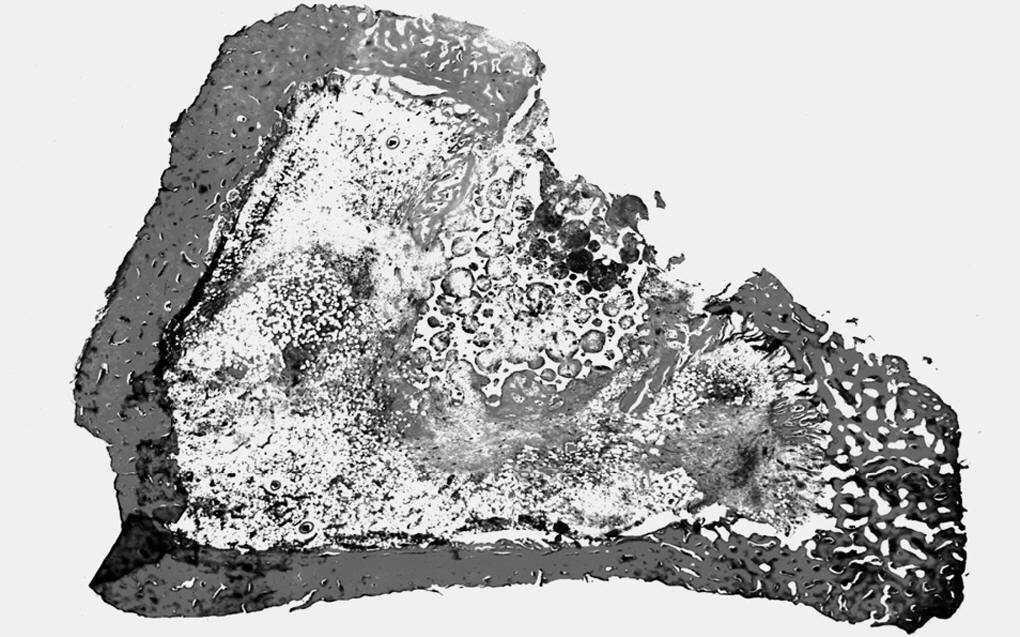

Estudio morfológico. La zona del implante mostró características superponibles al grupo anterior, destacando la sustitución casi total del tejido de granulación, que tapizaba el defecto óseo, con tejido óseo trabecular neoformado. También observamos una mayor sustitución del implante con trabéculas óseas, que representaban entre el 40-50% del volumen. Sólo vimos escasos restos del material con características similares a las anteriormente descritas (fig. 5).

Figura 5. Zona del implante en la porción superior central. Solución de continuidad de la cortical. Trabéculas óseas neoformadas alrededor y en el interior del implante (↑) (HE, 25 x).

Con microscopia óptica y con el MEB destacó, con respecto al grupo anterior, la mayor abundancia de tejido óseo alrededor del implante y en el interior de los poros.